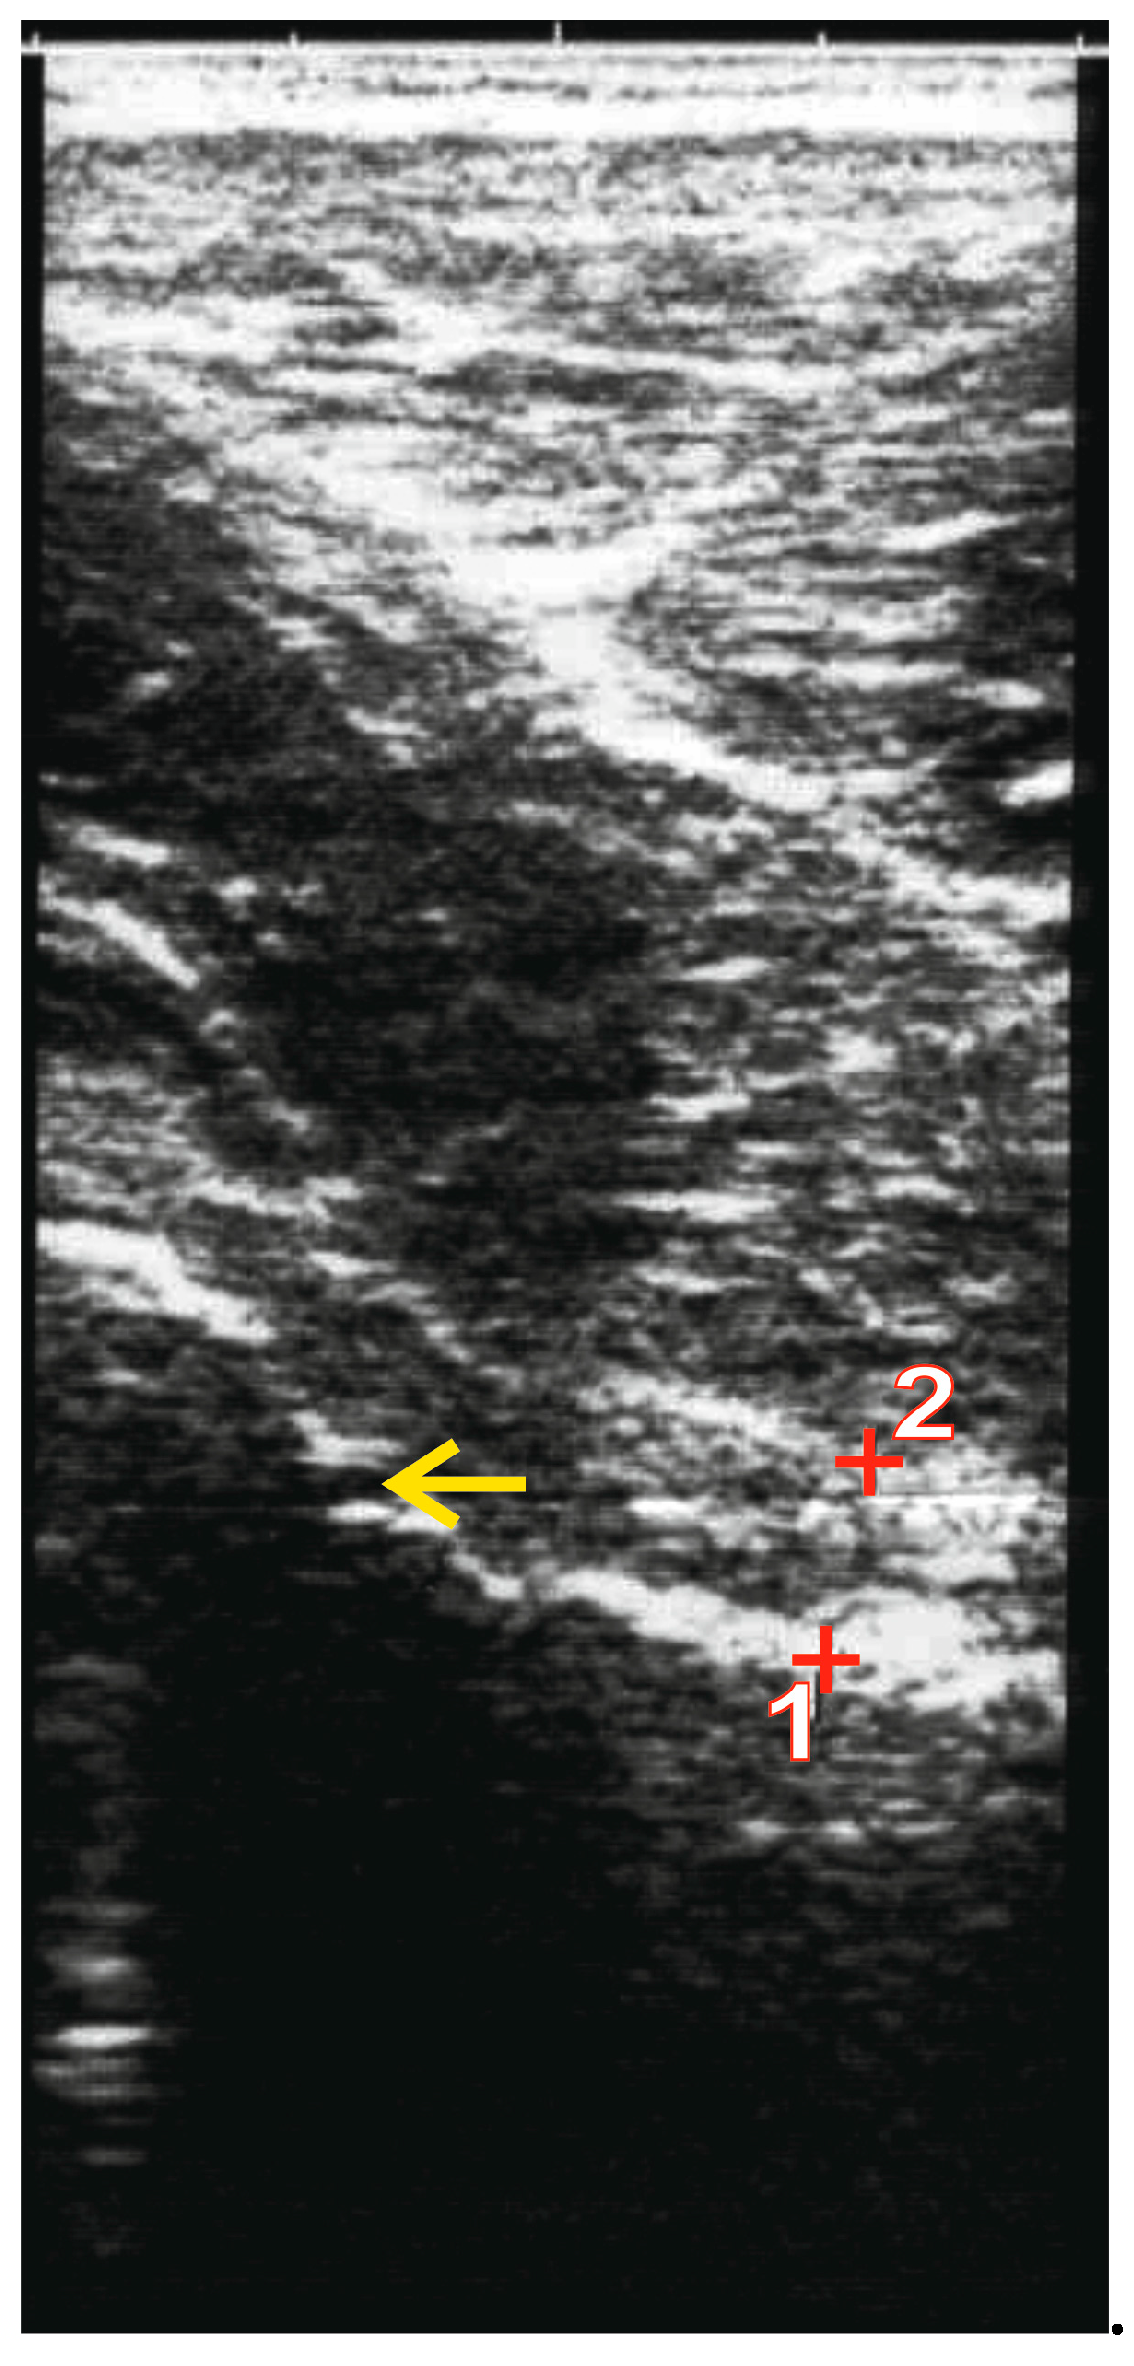

2.2. Imaging Procedures

- Irregularity at the femoral head–neck junction.

- Alpha angle > 60°.